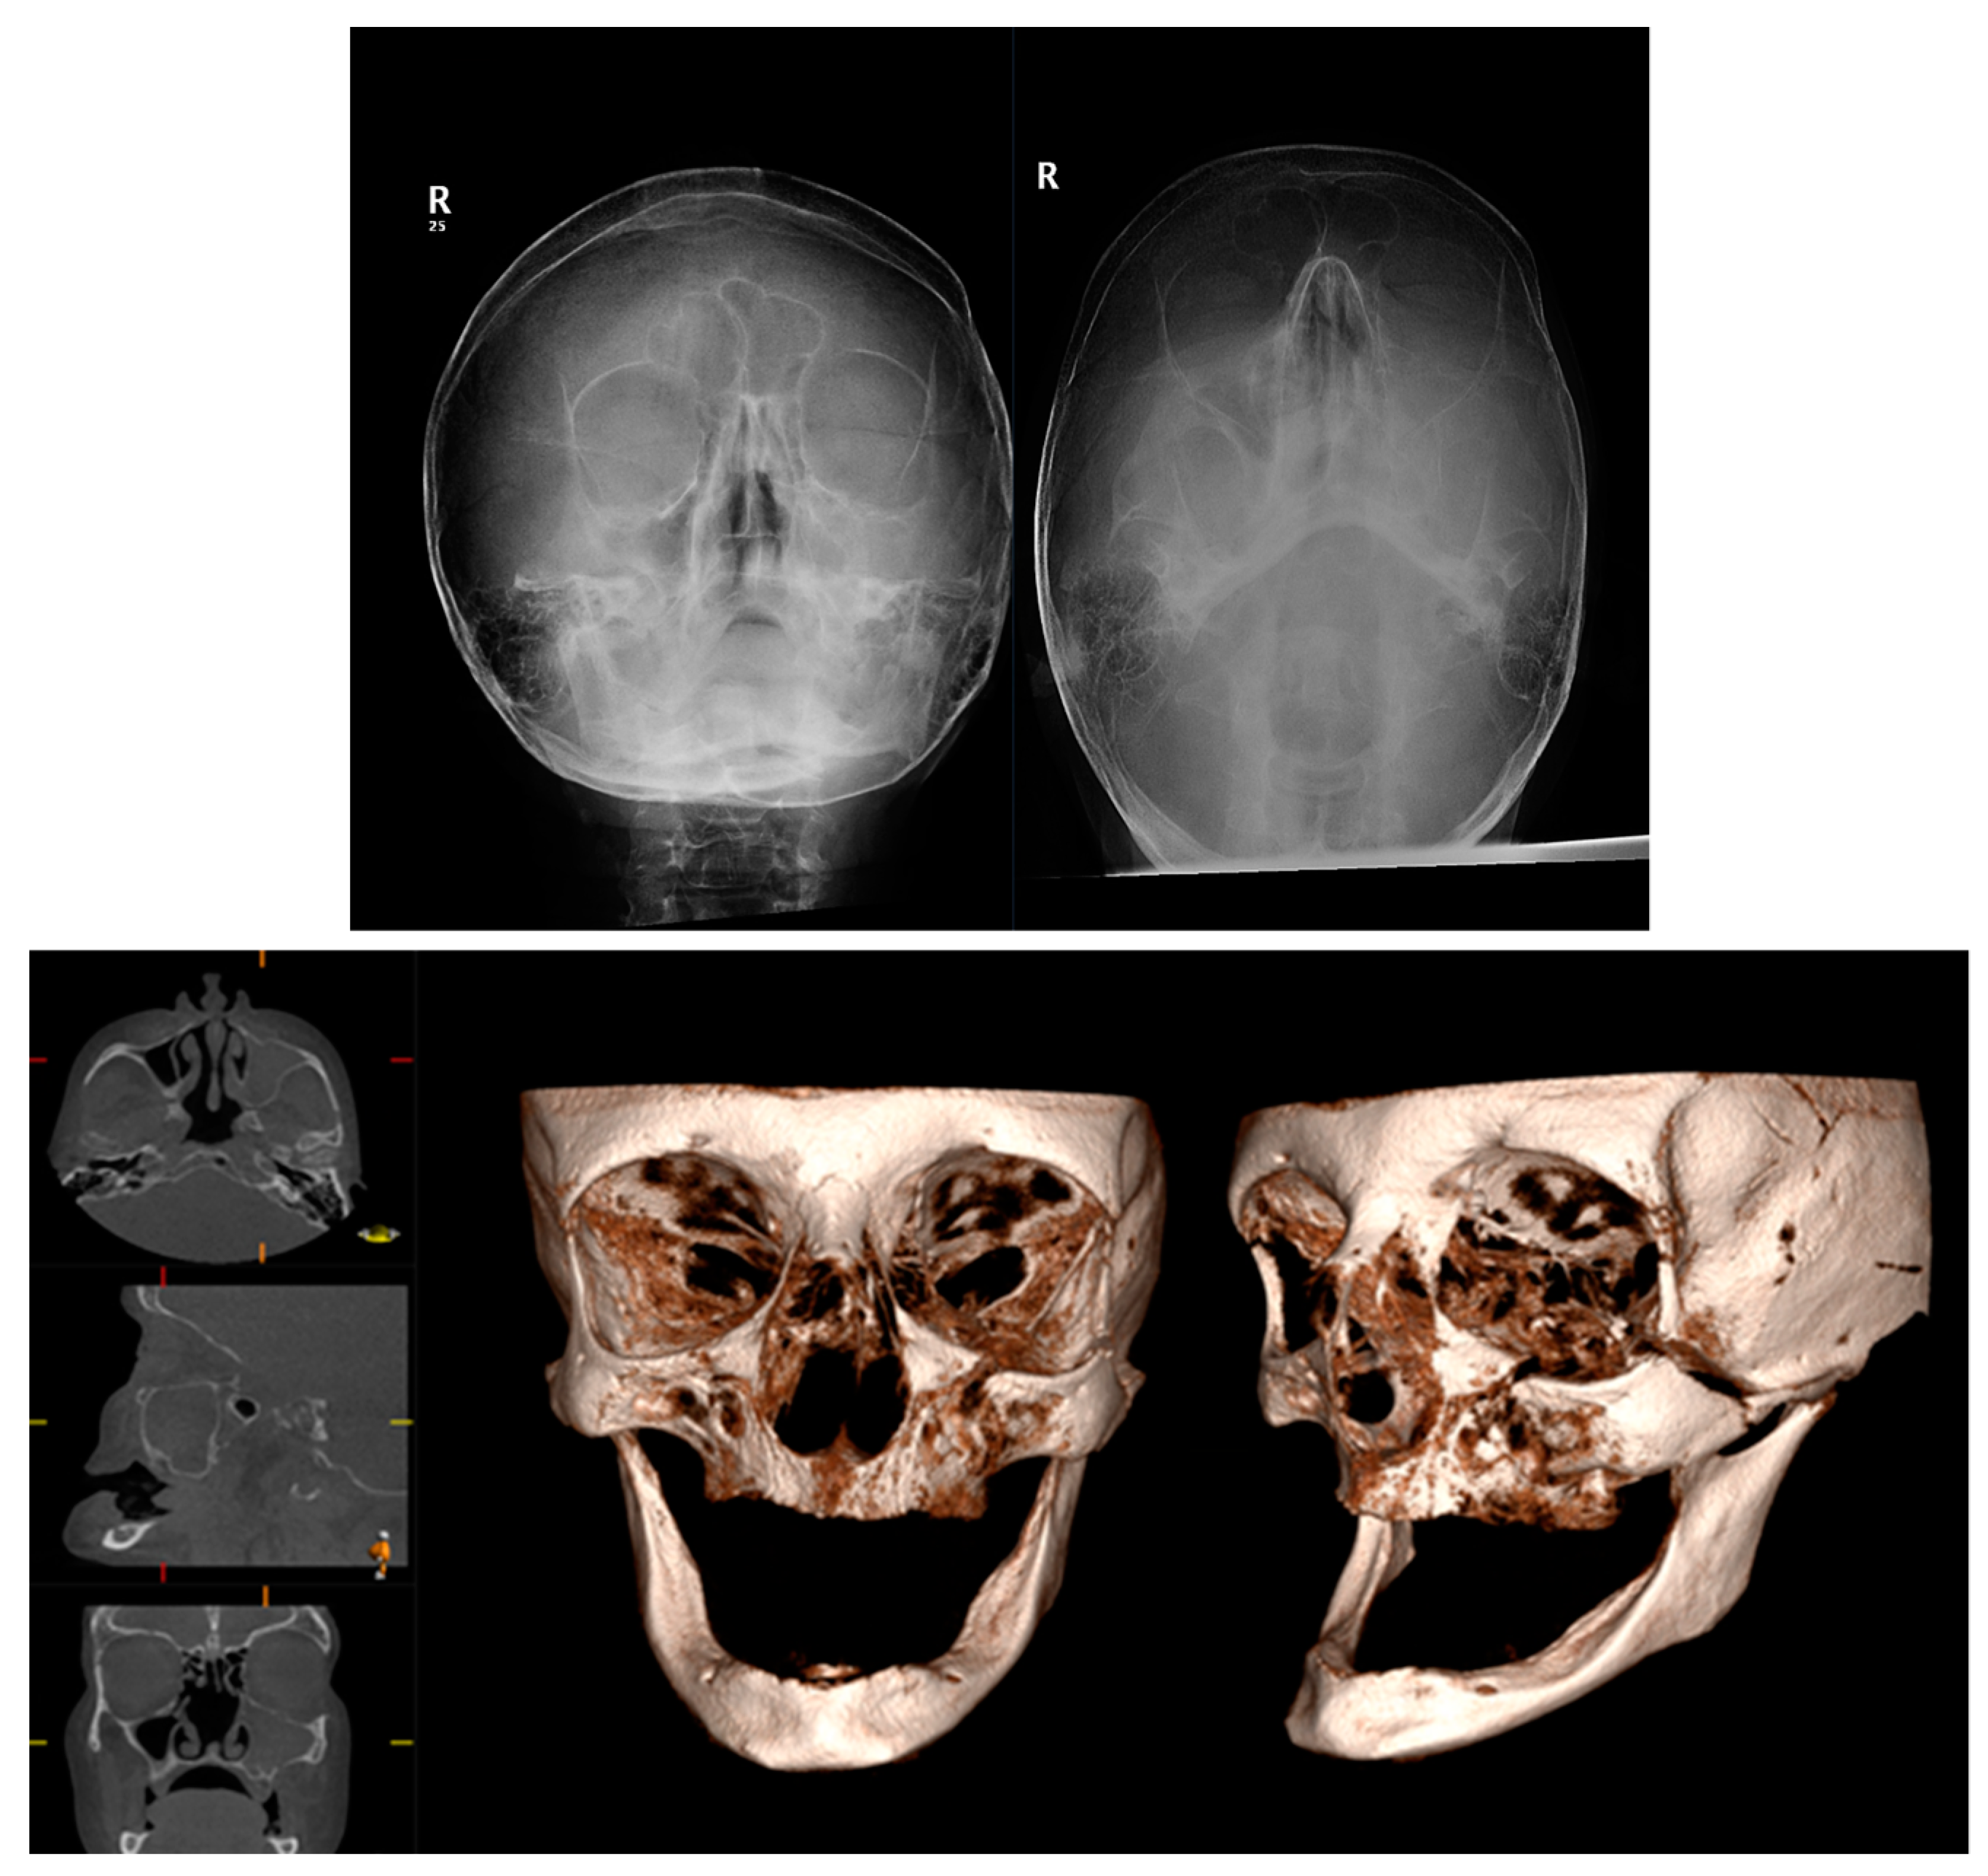

4. Intraoperative Use of CBCT in Surgical Management of Facial Fractures

| Heiland et al., 2005 [49] | Assessment of the adequacy of intraoperative CBCT | 14 patients undergoing surgical treatment for ZMC fractures | CBCT dataset generated and axial, coronal, and sagittal reconstructions evaluated by 5 examiners assessing 6 defined criteria. |

| Pohlenz et al., 2009 [54] | Describe the first clinical application of CBCT with an integrated flat-panel detector for ZMC fractures | 9 CBCT datasets of patients with a ZMC fracture were acquired intraoperatively using a mobile isocentric C-arm including a flat-panel detector | 4 OMFS surgeons and 2 radiologists evaluated each dataset regarding noise, transition, and delineation of landmarks. |

| Singh et al., 2015 [56] | Describe the use of intraoperative CBCT C arm for ZMC malpositioning | 1 case ZMC malpositioning in a patient with panfacial fractures | Case report |

| Alasraj et al., 2021 [57] | To determine how intraoperative CT affects the intraoperative revision rate | 22 patients underwent 25 intraoperative scans | Retrospective study. Primary outcome variable: immediate revision rate. Secondary outcome: total scanning time. |

| Gander et al., 2018 [58] | Assess the use of intraoperative CBCT for determining intraoperative revision rate and need for additional reconstruction of the orbit | 47 consecutive patients with simple or complex ZMC fractures | Retrospective analysis. Intraoperative CBCT (Xoran Technologies, Ann Arbor, MI, USA) was overlaid on preoperative image using iPlan software (Brainlab, Feldkirchen, Germany). |

| Cuddy et al., 2018 [59] | To quantify the effect of intraoperative CT on surgical decision making | 161 patients, consecutive recruitment | Retrospective case series; level 1 trauma centre. |